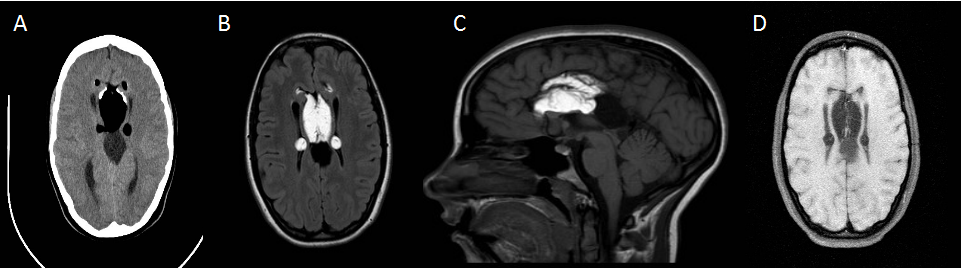

TC axial sin contraste (imagen A): lesión de 4 cm de diámetro máximo y densidad grasa en la cisura interhemisférica (asterisco), con calcificaciones groseras periféricas (flecha hueca). Se evidencia además agenesia del cuerpo calloso (flecha roja) y otra lesión, inmediatamente posterior, bien definida y de densidad similar al LCR (flecha blanca).

RM T1-WI axial y sagital (imagen B y C): lesión hiperintensa en la cisura interhemisférica (asterisco) con septos finos, agenesia del cuerpo calloso (flecha roja) y lesión nodular hipointensa (flecha blanca), localizada más posteriormente.

RM T1-WI fat-sat axial (imagen D): Supresión de la señal de la lesión de mayor tamaño (asterisco), compatible con contenido de grasa.

Agenesia completa del cuerpo calloso con lipoma pericalloso túbulo-nodular voluminoso y quiste de la cisura interhemisférica asociado.